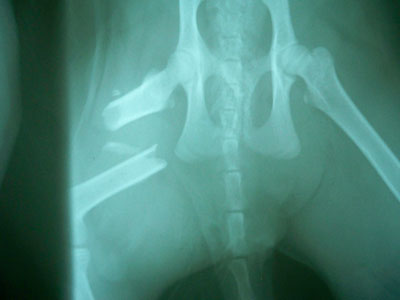

Γάτος ηλικίας 7 μηνών με κάταγμα μεσότητας διάφυσης μηριαίου οστού .Πραγματοποιήθηκε ορθοπεδικό χειρουργείο με μεταλική πλάκα κοχλίες και ορθοπεδικό σύρμα. Η αποκατάσταση ήταν 100% τα υλικά αφαιρέθηκαν 3 μήνες μετα .